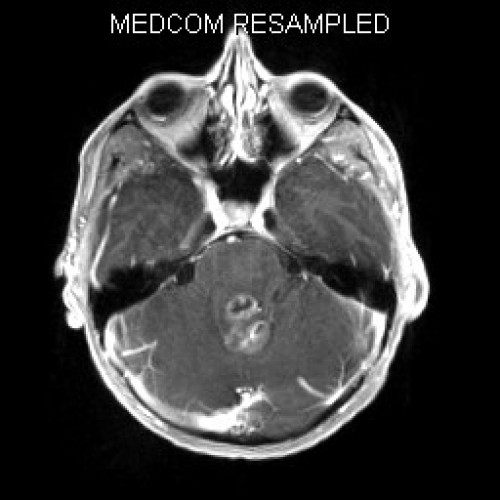

Müdigkeit und schlechte Noten

Fall-ID: 592

ICD: C75.3

ICD: G91.9

12-jähriger Junge. Die Eltern werden zu einem Gespräch bei der Klassenlehrerin gebeten, weil ihr Sohn sehr unaufmerksam geworden sei und seine Leistungen in der Schule bedenklich abgenommen hätten. Er droht das Klassenziel der 6. Klasse nicht zu erreichen.

Den Eltern war seit längerer Zeit bereits aufgefallen, dass sich ihr Sohn nach der Schule am liebsten ins Bett lege, um für eine Stunde einen Mittagsschlaf zu halten.